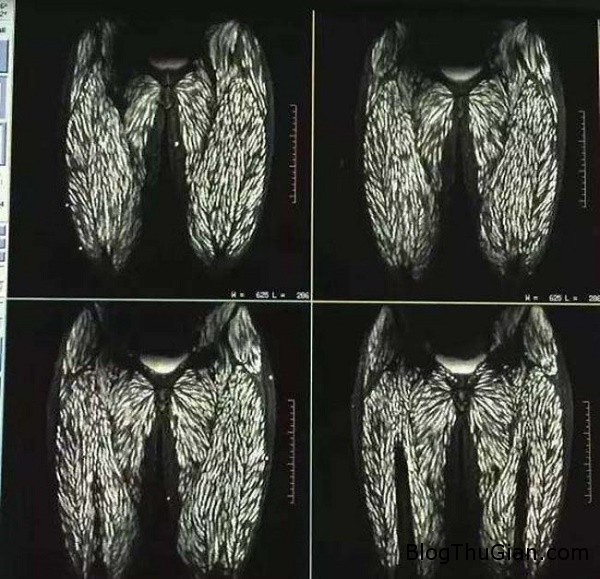

Đây là ảnh chụp x-quang của một người phụ nữ tại Trung Quốc. Toàn bộ cơ thể bà chứa đầy giun kí sinh và u nang vì ăn thịt lợn sống trong suốt 10 năm.

Thông thường một bộ não khỏe mạnh bình thường trên ảnh x-quang sẽ không có những chấm trắng như bức ảnh phía trên. Tên chính thức cho căn bệnh của bà là Cysticercosis (Bệnh ấu trùng sán lợn), gây ra bởi một loại sán dây có tên Taenia solium.

Loài sán ăn bám dày đặc trên 2 lá phổi của người phụ nữ.